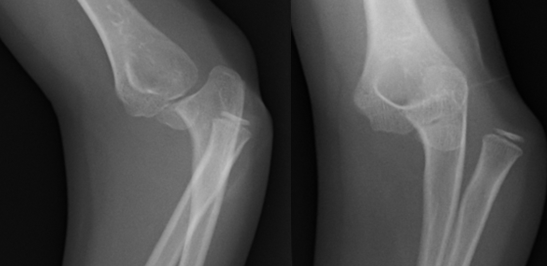

Ellenbogenluxation mit Sprengung des proximalen radio-ulnaren Gelenkes bei einem 7-jährigen Mädchen.